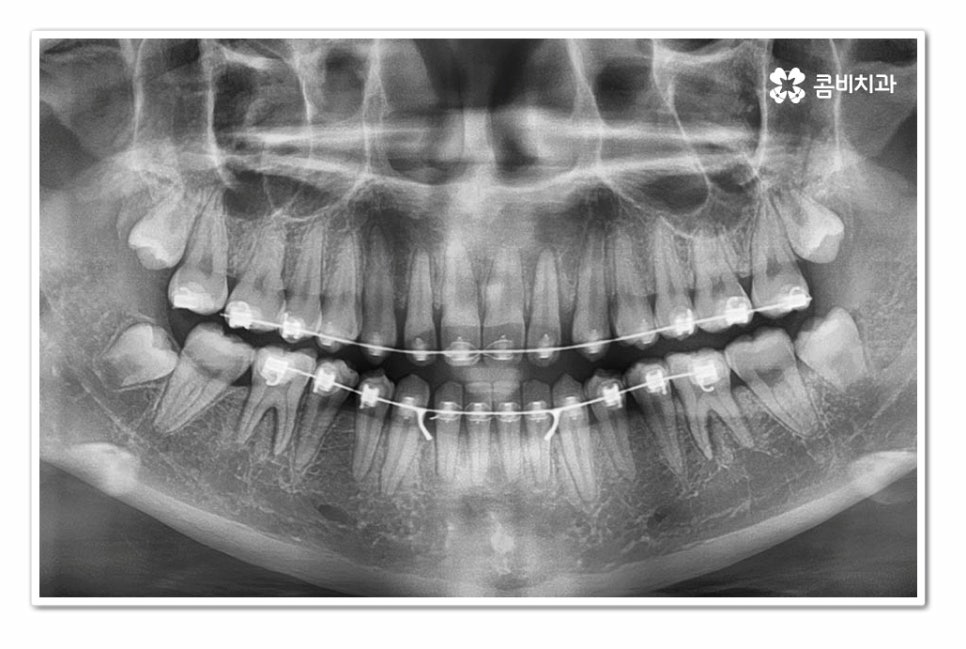

오늘 보여드린 환자분의 케이스는 윗니와 아랫니가 모두 벌어져 있기 때문에

전체교정을 통해서 치료가 진행되었지만

앞니 벌어짐 정도가 심하지 않거나 나이가 들면서 치아가 벌어진 분들의

경우에는 앞니만 부분교정이 가능한 경우가 있고

부분교정의 경우 심미성이나 치료 기간 등에 있어서

전체교정에 비해 부담이 크게 줄어든다고 할 수 있어요.